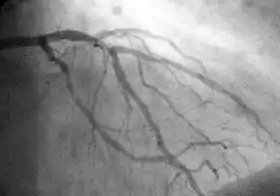

![]() Showing the coronary arteries that are subject to narrowing - resulting in reduced blood supply to the cardiac muscle. | |

PCI is used to open a blocked coronary artery/arteries and to restore arterial blood flow to heart muscle, without requiring open-heart surgery. In patients with acute coronary syndromes, PCI may be appropriate; guidelines and best practices are constantly evolving.[5] Heart attack 'onset to treatment time' is important and significantly influences clinical outcomes of PCI procedures. The rapid reperfusion of heart muscle is critical in preventing further heart muscle damage caused by heart attacks, this time is often referred to as 'Onset-to-Door' and 'Door-to-balloon' time, shortening this time is an important goal within an emergency care/ hospital setting. A number of initiatives have been active sponsored by a variety of organizations and hospital groups since the late 1990s to reduce this time to treatment.[6]